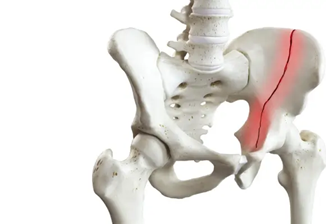

انواع شکستگی لگن

- شکستگی لگن معمولا در قسمت بلندی مفصل ران و در محل های مختلف اتفاق می افتد. گاهی اوقات سوکت یا ورق می تواند شکسته شود.

- شکستگی گردن فمور: این نوع شکستگی در استخوان ران در حدود 1 یا 2 اینچ اتفاق می افتد، جایی که سر استخوان به سوکت متصل می شود. شکستگی گردن فمورال ممکن است با ریختن عروق خونی، گردش خون را به توپ حامل خود برساند.

- شکستگی مفصلی: نوعی از شکستگی لگن است که شکستگی در ناحیه ای بین دو طرفه رخ می دهد.

- شکستگی داخل شکمی: این شکستگی قسمت های توپ و سوکت لگن شما را تحت تاثیر قرار می دهد. همچنین می تواند باعث انقباض عروق خونی که به توپ برود، منجر شود.